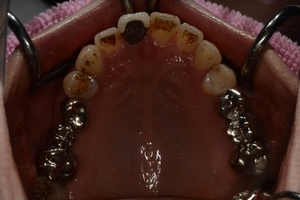

〇ご相談内容:歯並びがよくない〇矯正の種類:マウスピース型矯正「インビザライン」〇治療期間:39週間〇治療費用:44万円(税込)